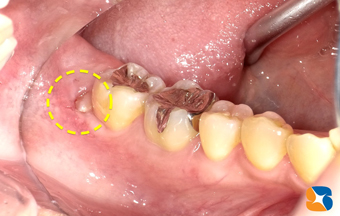

少しだけ頭を覗かせる親知らず

コラム「少しだけ頭を覗かせる親知らず」の画像